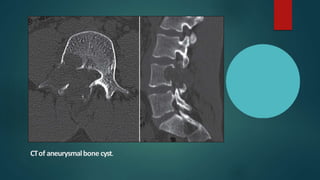

CTof aneurysmalbone cyst.

Computed Tomography

• Cross-sectional CT is the most useful imaging examination, because

it can demonstrate the intraosseous and extraosseous extents of the

lesion.

• CT can be used to determine the nature of the matrix of the tumor,

especially when tumors are in complex locations, such as the facial

skeleton, spine, thoracic cage, and pelvis.

• Spinal CT can demonstrate stenosis of the spinal canal due to

involvement of the posterior elements.

Computed tomography of cervical spine with three-dimensional reconstruction

showing destruction of body and posterior elements of C3 vertebra with partial

destruction of body and posterior elements predominantly on the left side of C2

and C4 vertebrae

CT scan of aneurysmal bone cyst arising from lamina and internal mass of C6

resulting in a unilateral dislocation of the facet joints in a 10 year old girl.